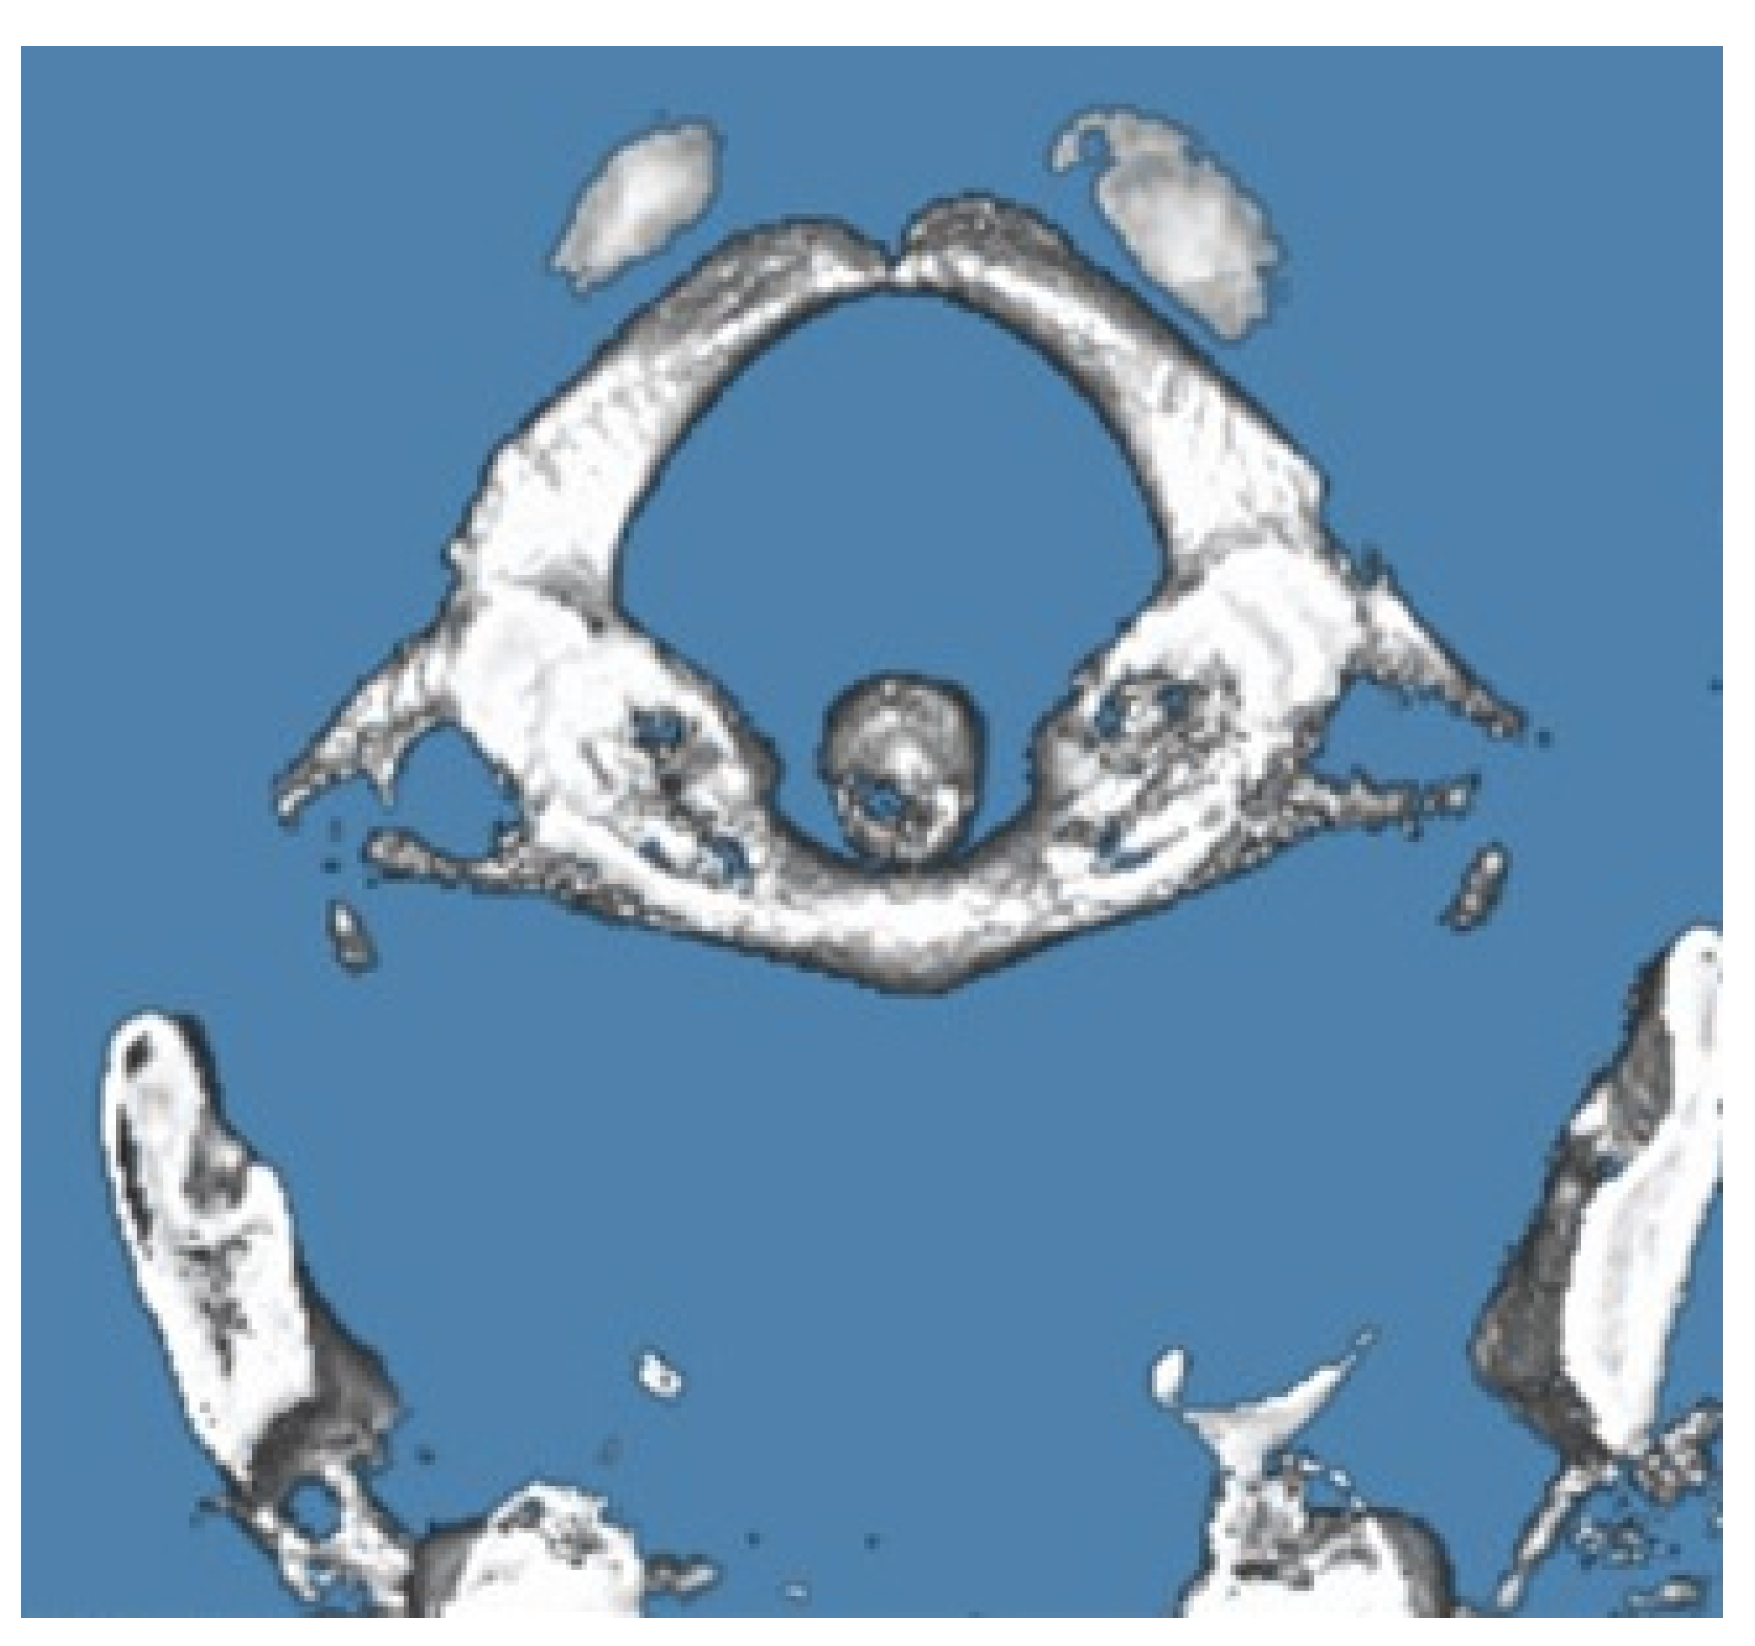

Classification and Measurement: APAD was classified according to the system proposed by Currarino et al. (1994) and illustrated in Figure 1, which categorizes anomalies into five types based on morphological characteristics:

• Type A: Failure of posterior midline fusion of the two hemiarches

• Type B: Unilateral defect

• Type C: Bilateral defects

• Type D: Absence of the posterior arch with a persistent posterior tubercle

• Type E: Absence of the entire posterior arch, including the tubercle

Figure 1. Classification of posterior arch defects of the atlas. Adapted with permission from Currarino G, Rollins N, Diehl JT: Congenital defects of the posterior arch of the atlas: A report of seven cases including an affected mother and son. AJNR Am J Neuroradiol 1994, 15, 249–254.